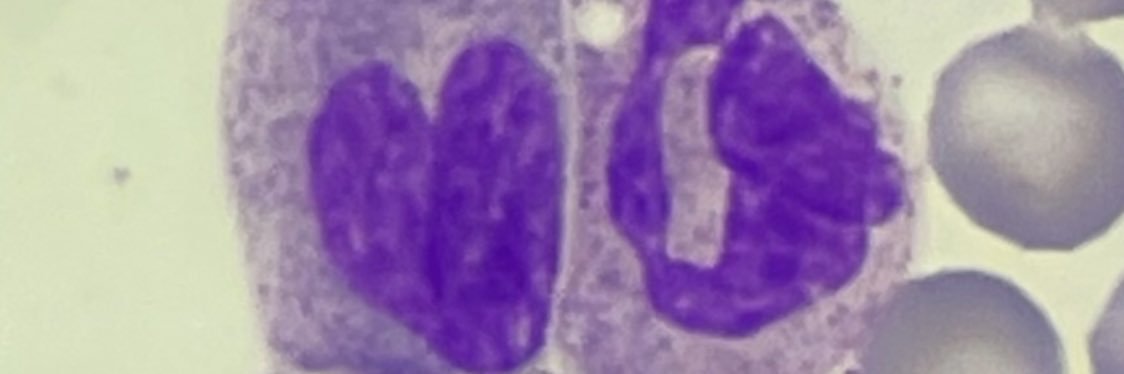

🔬 #fêtedelascience @LvvNumerique M. le Recteur et @v_guggiari à la rencontre d'élèves en STL animateurs d'ateliers à destination de 2nd dans le domaine des biotechnologies 🗣 échanges avec des étudiants #CPGE en ECP et ECT #ambition #réussite